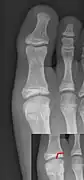

Salter–Harris I fracture of distal radius. -